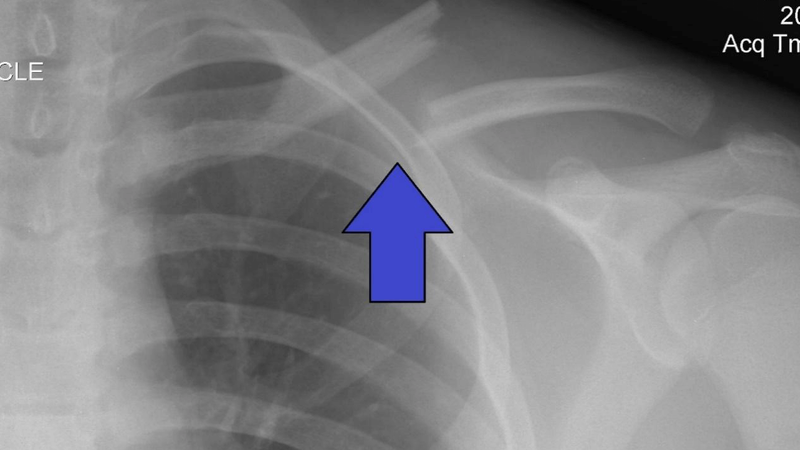

Gãy xương đòn là tổn thương thường gặp trong gãy xương, đặc biệt là ở độ tuổi thanh thiếu niên. Tùy từng trường hợp bác sĩ sẽ có chỉ định điều trị phù hợp. Vậy khi nào gãy xương đòn được chỉ định mổ và chi phí phẫu thuật gãy xương đòn hết bao nhiêu?

Phẫu thuật gãy xương đòn giúp người bệnh có thể nhanh chóng hồi phục. Trong các trường hợp dưới đây, người bệnh sẽ được bác sĩ chỉ định thực hiện phẫu thuật: